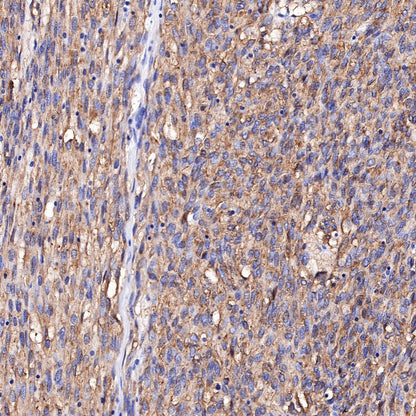

IHC shows positive staining in paraffin-embedded human gastrointestinal stromal tumor.

Anti-CD117 antibody was used at 1/1000 dilution, followed by a Goat Anti-Rabbit IgG H&L (HRP) ready to use.

Counterstained with hematoxylin.

Heat mediated antigen retrieval with Tris/EDTA buffer pH9.0 was performed before commencing with IHC staining protocol.